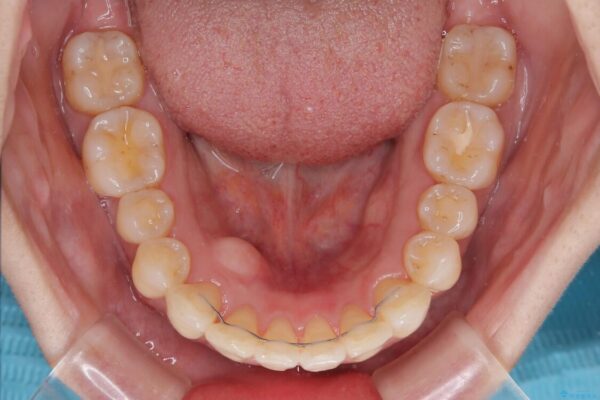

治療前

• インビザラインによる矯正治療と奥歯のインプラント治療 治療前画像

治療途中

• インビザラインによる矯正治療と奥歯のインプラント治療 治療途中画像